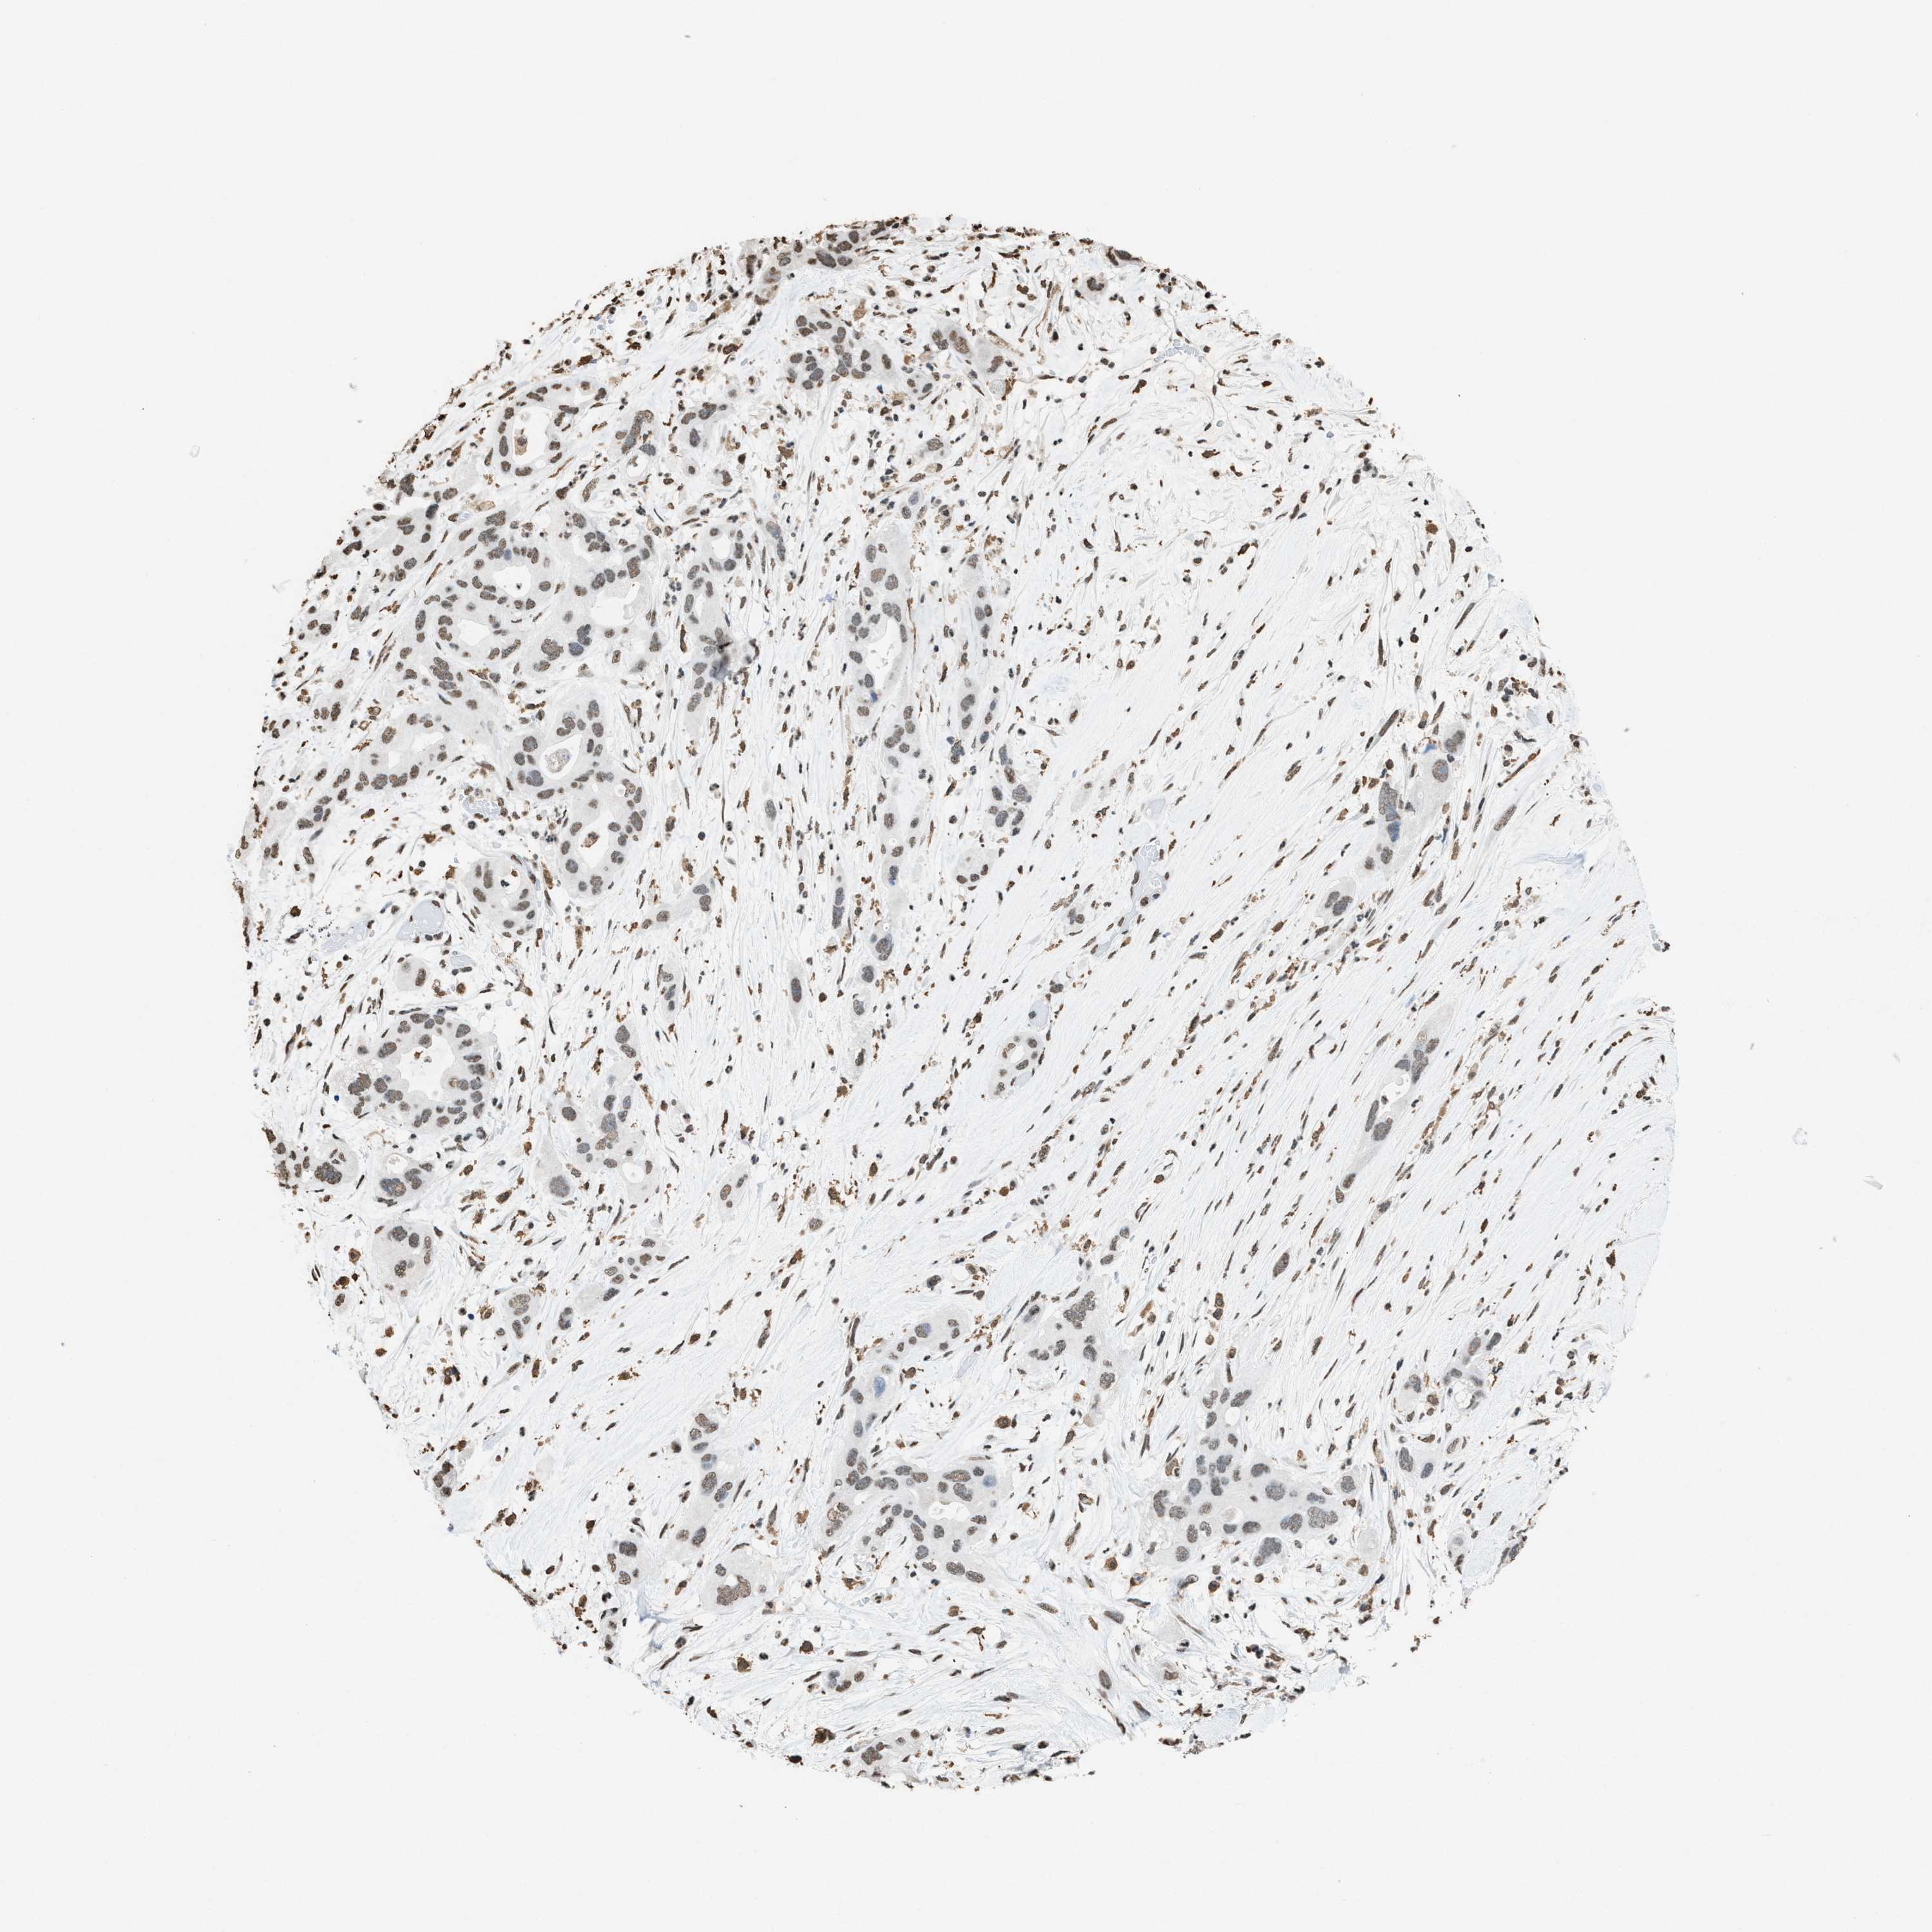

PANCREATIC CANCER - Protein expressioni

A mouse-over function shows sample information and annotation data. Click on an image to view it in a full screen mode. Samples can be filtered based on level of antibody staining by selecting one or several of the following categories: high, medium, low and not detected. The assay and annotation is described here.

Note that samples used for immunohistochemistry by the Human Protein Atlas do not correspond to samples in the TCGA dataset.

Antibody stainingi

Antibody staining in the annotated cell types in the current human tissue is reported as not detected, low, medium, or high, based on conventional immunohistochemistry profiling in selected tissues. This score is based on the combination of the staining intensity and fraction of stained cells.

Each image is clickable and will lead to virtual microscopy that enables deeper exploration of all samples and also displays staining intensity scores, fraction scores and subcellular localization as well as patient and tissue information for each sample.

Antibody HPA021816

Antibody CAB002209

Staining

High

Medium

Low

Not detected

Intensity

Strong

Moderate

Weak

Negative

Quantity

>75%

75%-25%

<25%

None

Location

Nuclear

Cytoplasmic/membranous

Cytoplasmic/membranous,nuclear

Adenocarcinoma, NOS

Adenocarcinoma, metastatic, NOS